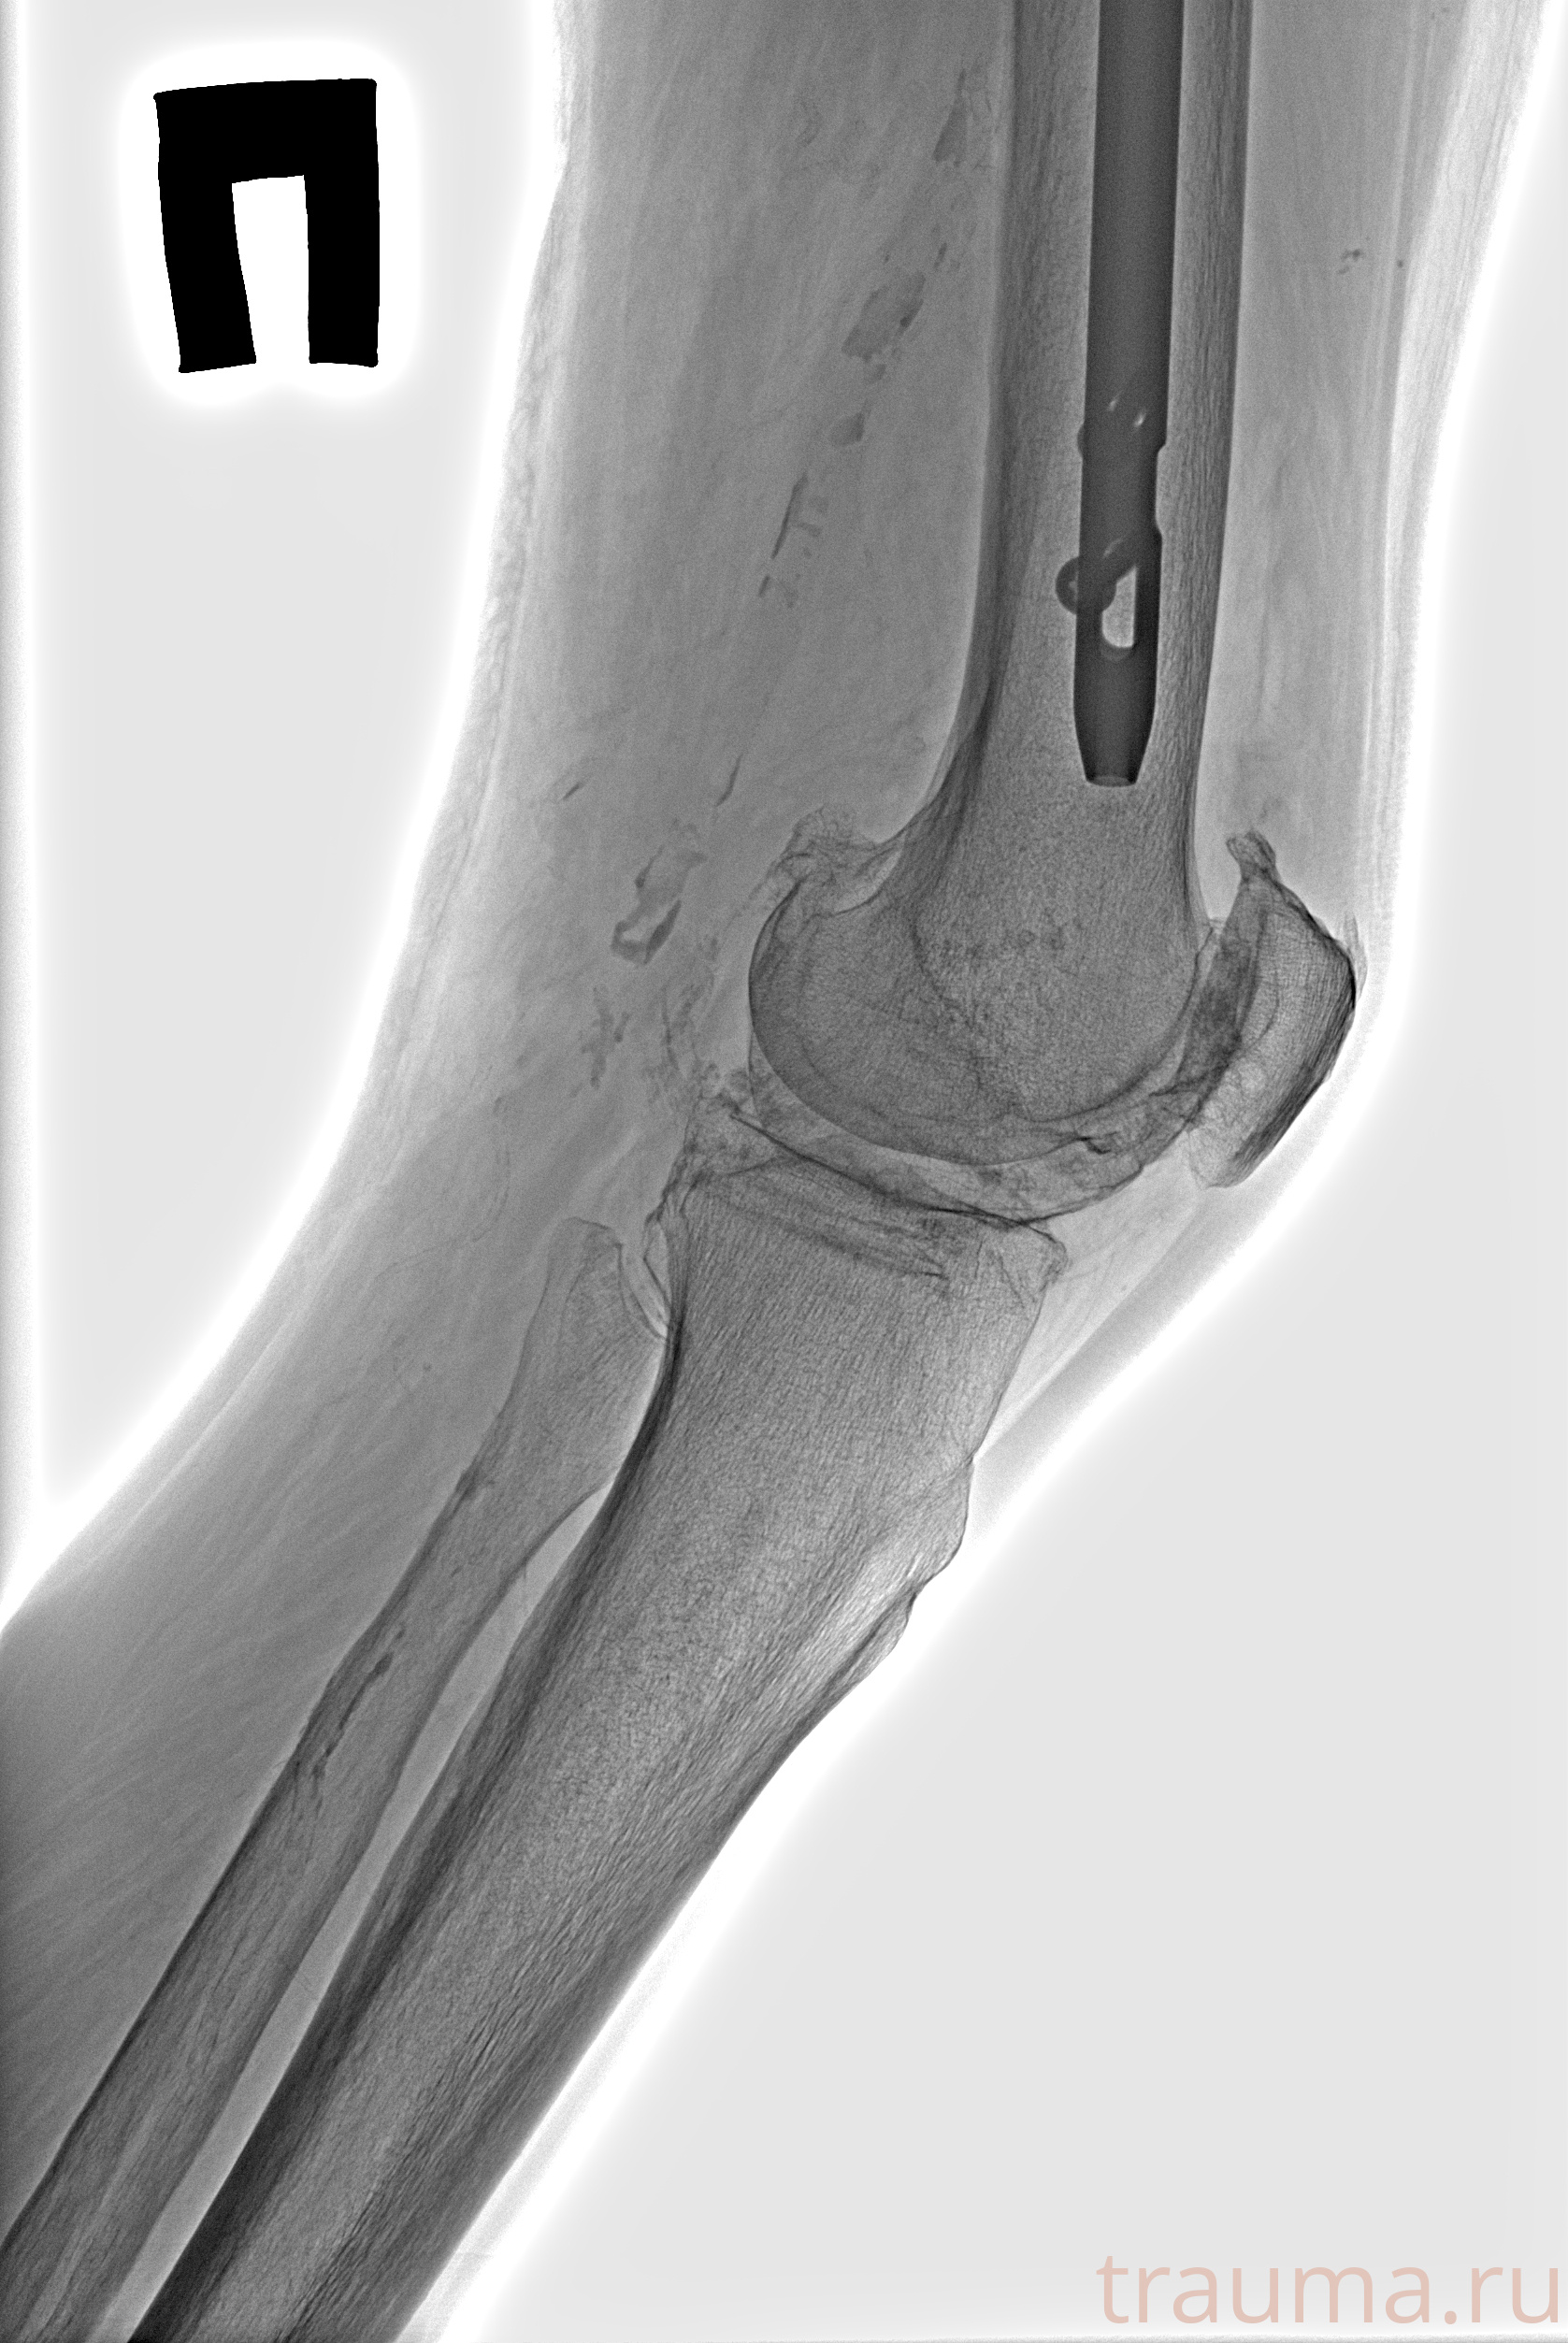

Рентгенограммы

Рентген на дому: по вашему адресу приезжает врач-рентгенолог, травматолог-ортопед с мобильным рентгеновским аппаратом, проводит диагностику травмы или заболевания, делает необходимые рентгенограммы, дает рекомендации по дальнейшему лечению. Получить качественные снимки в домашних условиях возможно благодаря уникальной методике, разработанной МосРентген Центром для института  Склифосовского